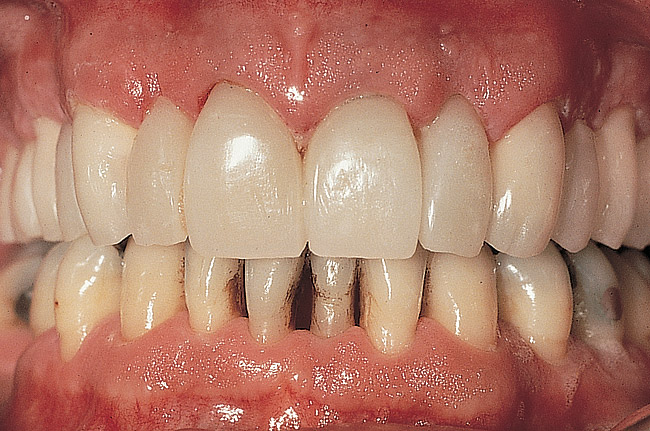

Figure 12  Preoperative facial view demonstrating maximum tooth display.

Figure 12